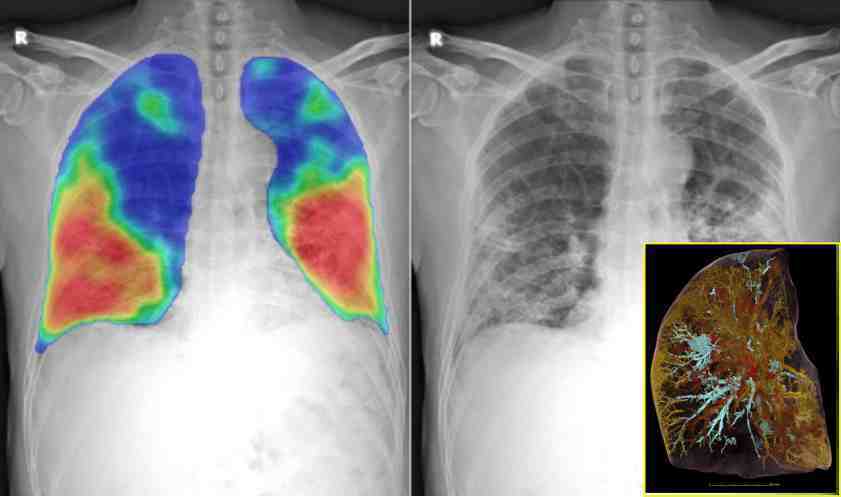

ذراتی اسراع گر(پارٹیکل ایسلریٹر) کی مدد سے تیار کردہ اس ٹکنالوجی کو ’ہیئرآرکیکل فیز کنٹراسٹ ٹوموگرافی Hierarchical Phase Contrast Tomography‘ (HiP-CT) کا نام دیا گیا ہے۔ اب یہ تمام جسمانی اعضا کی باریک ترین تفصیلات کو تھری ڈی انداز میں ظاہر کرتی ہے۔ سب سے پہلے اسے کوویڈ سے فوت شدہ ایک مریض کے پھیپھڑے پر آزمایا گیا ے جس میں خون کی نالیوں میں آکسیجن رکنے کا منظر بھی دیکھا گیا ہے۔

ایکسرے ٹکنالوجی یوروپی سنکروٹرون ریسرچ مرکز (European Synchrotron Research Facility) میں وضع کی گئی ہے جہاں دنیا کی روشن ترین ایکسرے حاصل کی گئ ہے جو روایتی ایکس رے سے 100 ارب گنا طاقتور ہے۔ کورونا وبا کے دوران اس پر سنجیدگی سے کام شروع کیا گیا-اب یہ حال ہے کہ اس سے خون کی باریک ترین نالیوں کو تھری ڈی انداز میں دیکھا جاسکتا ہے بلکہ بعض اقسام کے خلیات بھی دکھائی دینے لگتے ہیں۔

امید ہے اس ٹکنالوجی سے کوویڈ covid-19 میں پھیپھڑوں پر ہونے والے نقصانات اور دیگر تفصیل کو بھی سمجھنے میں بھی مدد ملے گی۔ اگلے مرحلے میں مشین اکتساب اور مصنوعی ذہانت سے مزید بہتر انداز میں تشخیص میں مدد مل سکے گی۔ تاہم ماہرین کی اکثریت نے اس کام کو غیرمعمولی انقلاب سے تعبیر کیا ہے